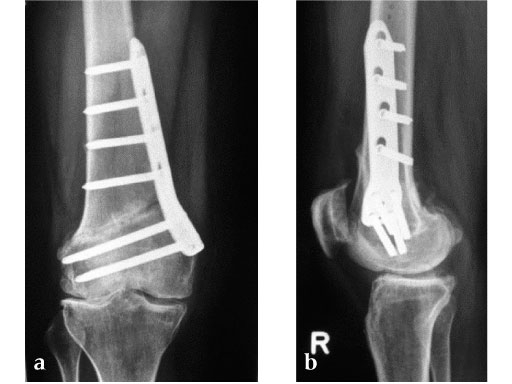

27-year-old male developed severe lateral joint line pain after lateral menicectomy.

Case provided by Philipp Lobenhoffer, Hannover, DE

An anteromedial skin incision is used. This skin incision can be reused and expanded during subsequent knee surgery. The vastus medialis muscle is dissected from the septum, the medial patellofemoral ligament (MPFL) and the distal insertion of the vastus medialis muscle are partially incised. Two blunt Hohmann retractors are placed around the distal femur. The oblique osteotomy starts in the medial supracondylar area and ends in the lateral condyle, approximately 10 mm inside the lateral cortex. For guiding the closing wedge osteotomy of the distal femur a specific saw guide will be available soon. Alternatively, it is possible to use K-wires inserted under image intensifier control to mark the bone cuts. The saw cuts are made with retractors protecting the soft tissue and vessels. The wedge is removed and the height and depth of the osteotomy can be measured. At this time it is possible to make modifications concerning the wedge size. Closing the wedge must be done gradually by gentle compression of the lower leg laterally, and stabilizing the knee joint medially near the area of osteotomy. This may take several minutes to enable plastic deformation of the lateral cortex to close the osteotomy gap. Leg alignment is checked radiologically after closing with a rigid alignment bar positioned between hip and ankle center. The bar representing the weight-bearing line should pass the preoperatively defined mechanical axis. The plate is inserted from distal under the vastus medialis muscle. The distal drill holes are oriented in a 20 angle inclination on the frontal plane to avoid a posterior perforation of locking head screws in the distal femur. The distal four bolts are placed. A lag screw is positioned in the dynamic hole directly above the osteotomy for compression of the osteotomy site. The screw should be tightened carefully using the image intensifier. The plate is now fixed to the shaft with bolts monocortically, and the lag screw is replaced by a bolt bicortically. The wound is closed in layers after insertion of a drain. The patient is mobilized on the first day after surgery. Partial weight bearing is recommended for 6 weeks, active movement of the knee is enhanced. Biomechanical testing confirmed superior stability of medial closing wedge techniques as compared to lateral open wedge techniques and favourable axial and torsional loading characteristics of the TomoFix medial distal femur (MDF) plate. The plate is now available, as well as a booklet on the operative technique.